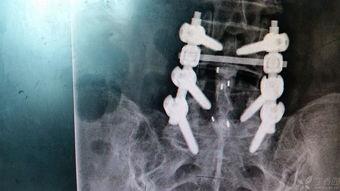

腰椎钉棒固定手术,听起来是不是有点高大上?其实,它就是医生们用来治疗腰椎骨折、腰椎滑脱等疾病的一种手术方法。简单来说,就是通过在腰椎上安装一些特殊的钉子和棒子,来稳定骨折的部位,让腰椎恢复正常的生理功能。

3. 植入钉棒:医生会通过切口,将特制的钉子和棒子植入到腰椎上。这些钉子和棒子就像一把把“锁”,能够牢牢地固定住骨折的部位。

4. 固定:在钉子和棒子植入后,医生会调整它们的位置,确保腰椎的稳定性。